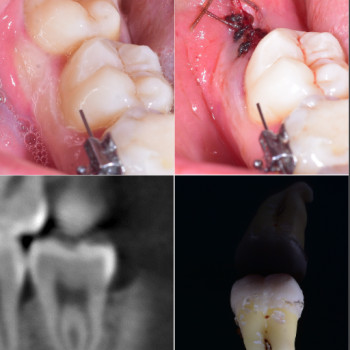

| ✅ Стоматолог Вепа Джумаев | 1300 грн |